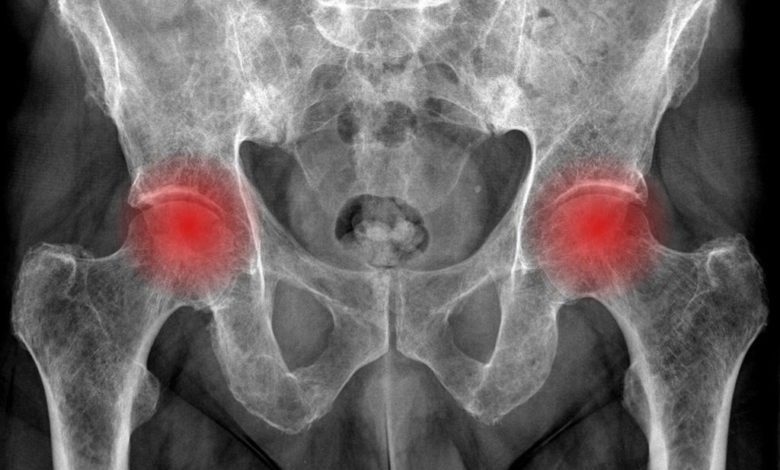

Femur başı avasküler nekrozu

Kalça ekleminin çok önemli bir sorunudur. Erken yaşlarda kalça eklemi artrozuna (kireçlenmesine) neden olabilir. Çok farklı nedenlerle (ilaç kullanımı, başka sistem hastalıkları ve tedavisi, travma vb) ortaya ikincil olarak çıkabileceği gibi bir grup hastada neden bulunamaz. Yüksek oranlarda çift taraflı görülebilir. Kalça oynarında, femur başında damarsal beslenme bozukluğu, kemiğin yapısında bozulma ve sonucunda çürüme meydana gelir. Hastalık kalça ve kasık bölgesi ağrısı, aksama ile başlar, önemsenmeyebilir, farklı tanılarla tedavisi atlanabilir ve de sıklıkla tanı konması gecikebilir. Normal grafilerde erken dönemde tanı konamayabilir ancak MR hastalığı erken evresinde de tanıyabilmektedir. Ayırıcı tanıda kendinden geçebilen transient(geçici) osteoporoz gibi bazı hastalıklar akılda tutulmalıdır. Kalça eklemi yük taşıyan bir eklem olup, tedavide gecikildiğinde oynarda çökmeler, kireçlenmeler olur ve eklem özelliğini yitirir. O zaman da tedavi de kalça eklemi protezi dışında bir alternatif kalmaz.

Bu hasta 43 yaşında her iki femur başı avasküler nekrozu tanısı almıştır. Sol tarafı, artık oynarın özelliğini, yitirdiği kireçlenmenin meydana geldiği çok ileri bir evrede iken, sağ tarafı Evre 2 C olarak sınıflandırılan daha erken evre hastalığı göstermektedir. MR görüntülerinde de hastanın femur başlarındaki hastalık süreci izlenmektedir. Bu hastanın erken evrede olan kalça oynarını kurtarmak için mikrocerrahi teknikle canlı kemik nakli (damarlı fibula nakli) ameliyatı yapılmıştır. Sol tarafı ise bu ameliyattan sonra kalça protezi ile tedavi edilmiştir. Erken evrede yakalanan sağ kalçanın canlı kemik nakli ile normal bir femur başı yapısına tekrar döndüğü görülmektedir. Damarlı fibula naklinin yapılması sonrası hasta 5. Yıl takibindedir. Sol taraf gibi sağ kalça ekleminin proteze ihtiyaç göstermesi engelenmiştir. Hastanın kendi eklemi korunmuştur.